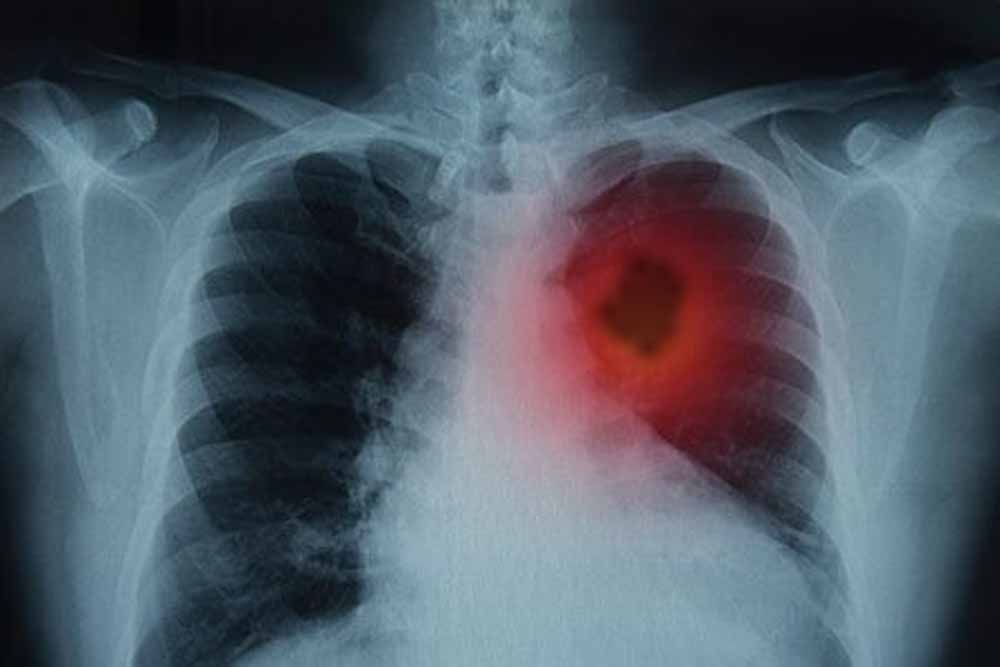

फेफड़ों के कैंसर से लड़ाई में नई उम्मीद! शोध में ट्यूमर 80% तक कम करने की सफलता

फेफड़ों के कैंसर से जूझ रहे लाखों लोगों के लिए विज्ञान की दुनिया से एक बहुत बड़ी और राहत भरी खबर आई है। दरअसल, वैज्ञानिकों ने एक ऐसा तरीका खोजा है जिससे फेफड़ों के ट्यूमर को उसकी सबसे बड़ी कमजोरी पर वार करके खत्म किया जा सकता है। जी हां, इस शोध के दौरान, उन्होंने एक बेहद जरूरी प्रोटीन की पहचान की। बता दें, यह प्रोटीन कैंसर कोशिकाओं को 'मरने' से बचाता है। ऐसे में, शोधकर्ताओं का कहना है कि अगर इस खास प्रोटीन की गतिविधि को रोक दिया जाए, तो कैंसर कोशिकाएं खुद-ब-खुद नष्ट होने लगती हैं और ट्यूमर सिकुड़ जाता है।

हाल ही में शोधकर्ताओं ने फेफड़ों के कैंसर की एक महत्वपूर्ण कमजोरी का पता लगाया है- एक ऐसा प्रोटीन, जिसे रोक दिया जाए तो कैंसर कोशिकाएं खुद को ही नष्ट करने लगती हैं। यह खोज न सिर्फ इलाज के नए रास्ते खोलती है, बल्कि भविष्य में ऐसे कई मरीजों के लिए जीवनदायिनी साबित हो सकती है, जिन्हें अब तक सीमित विकल्प ही उपलब्ध थे।

अमेरिका के एनवाइसी लैंगोन हेल्थ के वैज्ञानिक लंबे समय से यह समझने की कोशिश कर रहे थे कि आखिर क्यों कुछ कैंसर कोशिकाएं शरीर की रक्षा प्रणाली से बचकर बढ़ती चली जाती हैं। इसी खोज के दौरान उन्होंने एक खास प्रोटीन- एफएसपी1 (FSP1) की पहचान की।

यह प्रोटीन कैंसर कोशिकाओं को एक खास तरह की कोशिका मृत्यु, जिसे फेरोप्टोसिस कहा जाता है, से बचाता है। फेरोप्टोसिस वह प्रक्रिया है जिसमें शरीर अत्यधिक तनाव में आ चुकी कोशिकाओं को खुद-ब-खुद नष्ट कर देता है। आमतौर पर यह प्रक्रिया शरीर की सुरक्षा प्रणाली का हिस्सा है, लेकिन कैंसर कोशिकाएं इसी से बचकर बढ़ती रहती हैं।

शोधकर्ताओं ने चूहों पर प्रयोग करते हुए एफएसपी1 प्रोटीन को रोका। परिणाम इतने चौंकाने वाले थे कि उन्हें वैज्ञानिक ‘ड्रामेटिक’ कह रहे हैं।

चूहों के फेफड़ों में मौजूद ट्यूमर तेजी से सिकुड़ने लगे

कई कैंसर कोशिकाओं ने खुद को नष्ट करना शुरू कर दिया

कुल मिलाकर ट्यूमर का आकार लगभग 80% तक घट गया

यह परिणाम बताते हैं कि एफएसपी1 को निष्क्रिय करने से कैंसर कोशिकाओं के पास बचने का कोई रास्ता नहीं रहता और वे फेरोप्टोसिस की प्रक्रिया में फंसकर खत्म होने लगती हैं।